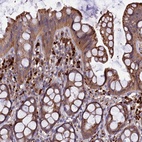

Immunohistochemical staining of human rectum shows moderate cytoplasmic positivity in glandular cells.